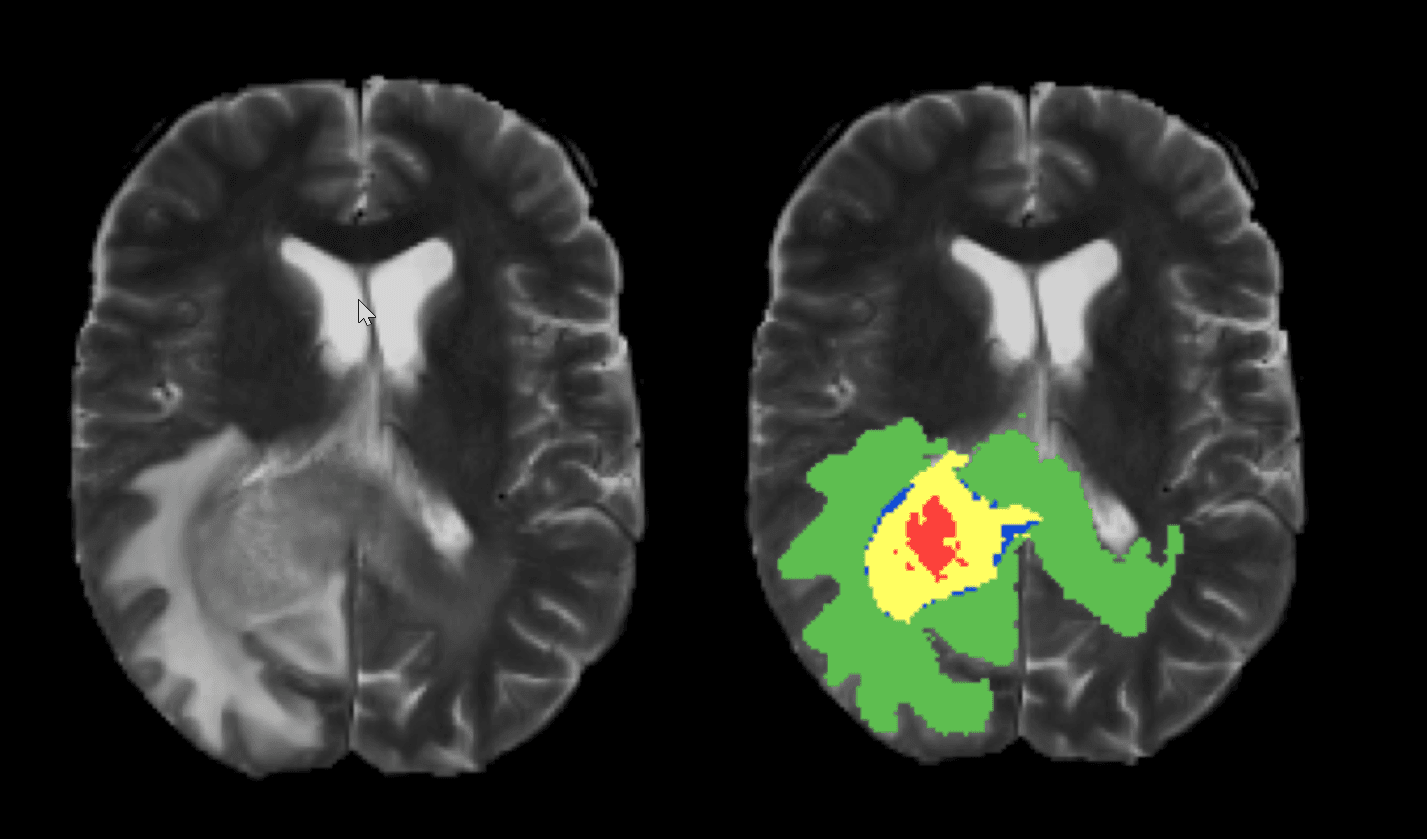

Medical MNIST